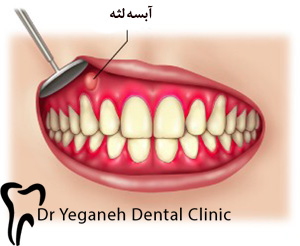

آبسه لثه

آبسه لثه معمولاً ناشی از عفونت در فضای بین دندان و لثه است. ممکن است عفونت پس از اینکه ذرات غذا بین لثه و دندان گیر افتادند، رخ دهد. در افراد مبتلا به بیماریهای شدید لثه، باکتریها میتوانند در زیر لثه یا داخل استخوان تجمع پیدا کنند.